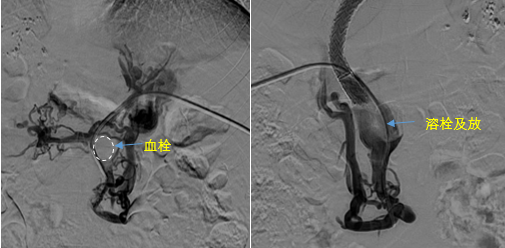

在西安國際醫學中心醫院,韓國宏教授對李女士進行了細致的問診及檢查,在CT圖像上仔細的分析,針對患者特殊的病情制定了詳細的治療方案。第一次進入手術室,在DSA的監測下,造影過程中門靜脈血栓的輪廓逐漸顯現出來,見多識廣的醫生們也大吃一驚,發現遠端脾靜脈及腸系膜上靜脈也存在大量血栓。患者的食管胃底靜脈曲張非常嚴重,疏通堵塞的門靜脈已是刻不容緩。

見此情形,韓國宏教授憑借豐富的臨床經驗很快調整了策略,在超聲診療中心的協助下進行門靜脈右支穿刺,并進行造影,看到目標血管后,韓國宏教授用“明修棧道,暗渡陳倉”的方法,讓來自脾臟和胃腸的血流終于暢通的回流到了肝靜脈。通過血流的沖刷以及抗凝溶栓藥物的作用,幾日后復查造影發現門靜脈血栓已逐漸變小,不會對回流到肝臟的血流產生大的阻礙作用,門靜脈的壓力顯著減小,患者再次出血的幾率也隨之降低。幾經周折,這顆“定時炸彈”終于被拆除,李女士和她的家人多年來心里的石頭也終于落地。